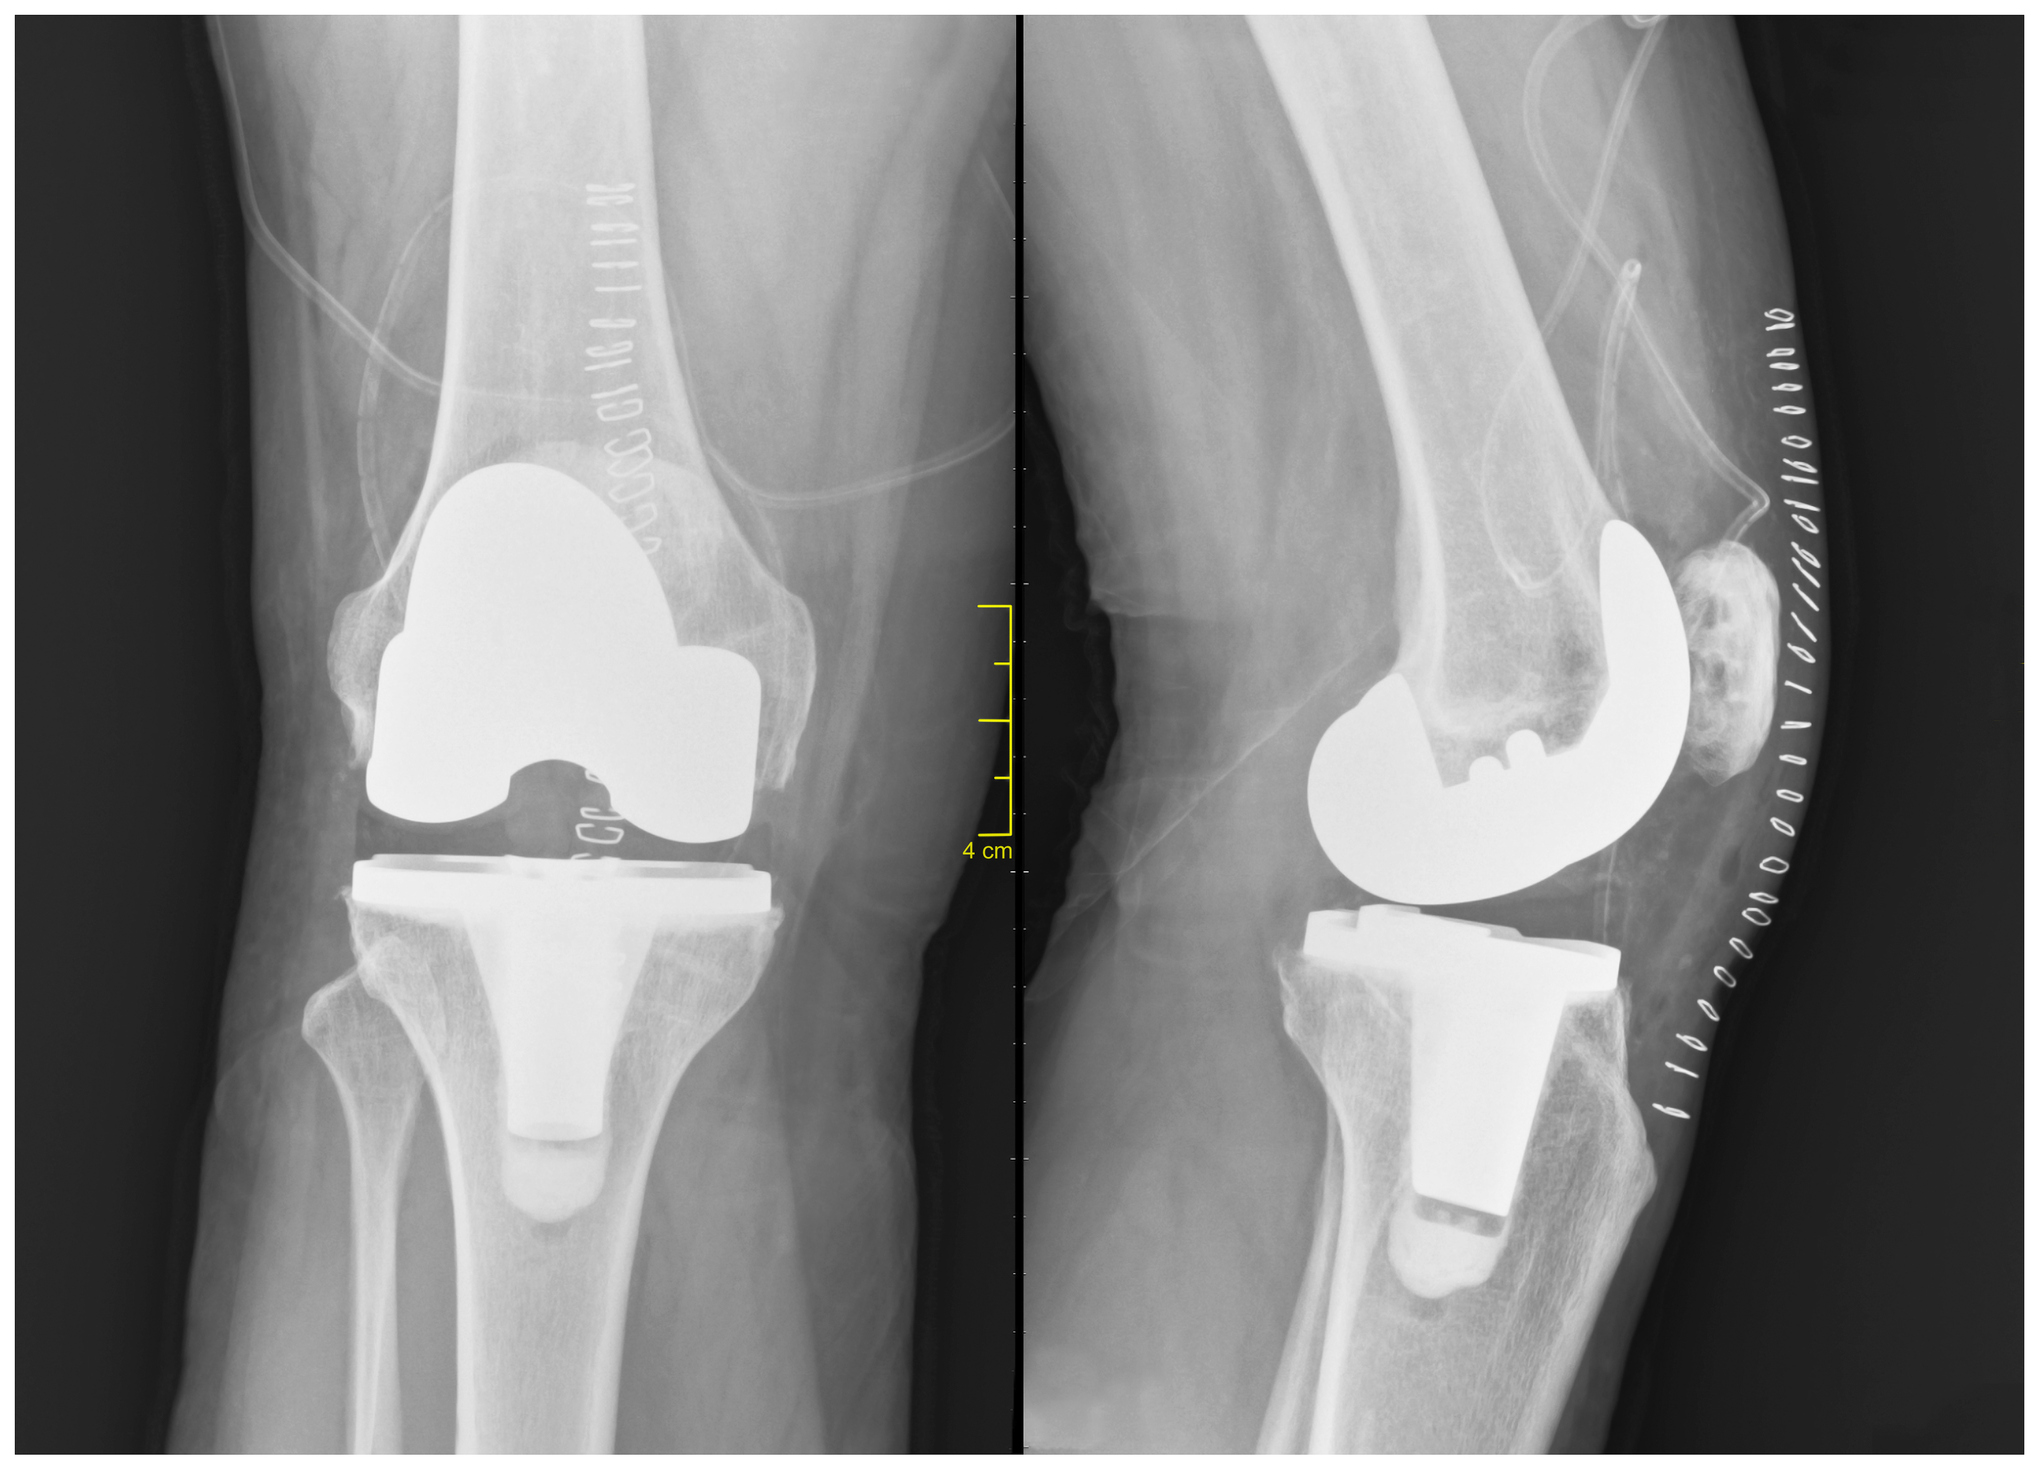

During a total knee replacement procedure, your orthopedic surgeon will remove the total damaged portion of the knee and replace it with a prosthetic joint, thereby getting rid of any part of the knee joint that is damaged or unhealthy.  The artificial knee joint is now your official knee joint; it will function either the same as a real knee or even better once full mobility is gained.